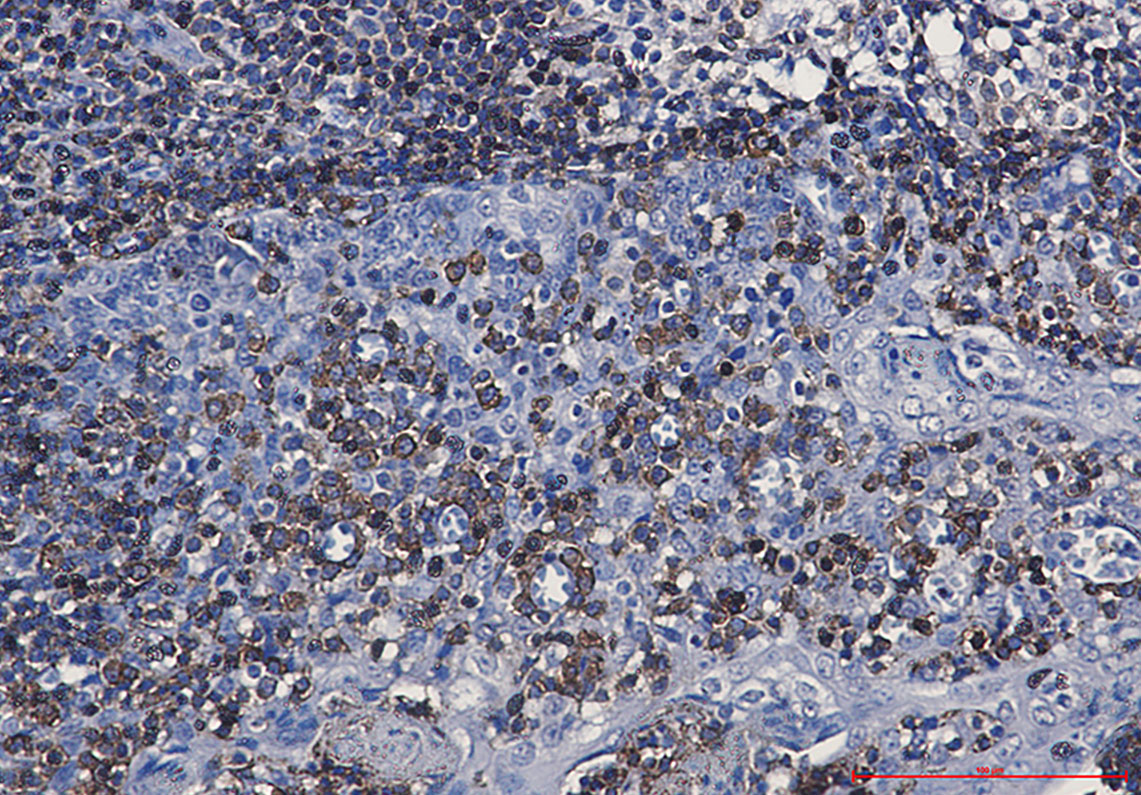

Product Image

- Immunohistochemistry analysis of paraffin-embedded Human tonsil using CD79a antibody. High-pressure and temperature Sodium Citrate pH 6.0 was used for antigen retrieval.